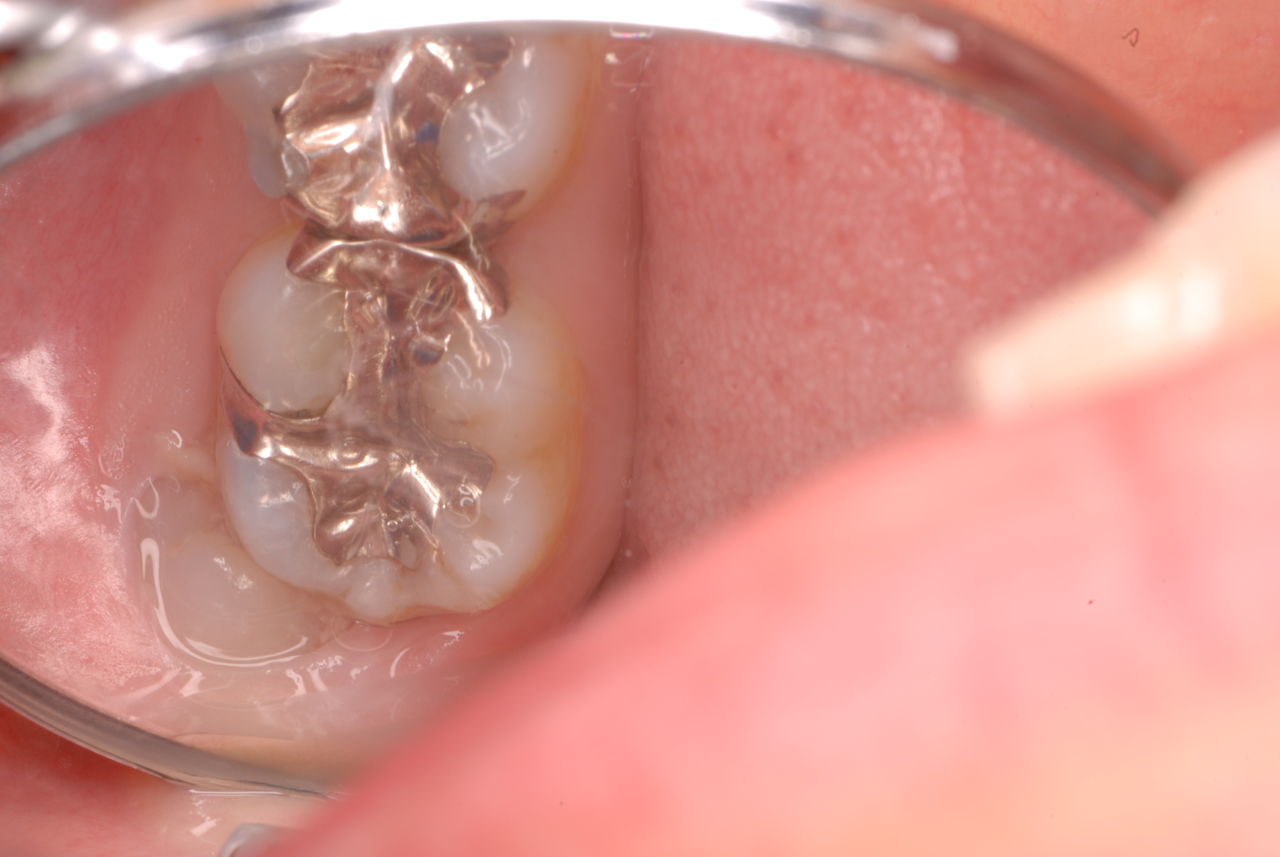

右下の歯は歯の中の治療もあやしいのですが、金属と歯の間がすでに虫歯で崩壊し始めています。

プラークというバイキンと毒素と食べかすの塊が歯の周りや歯茎にまとわりついて虫歯になり且つ重症の歯周病を患っています。